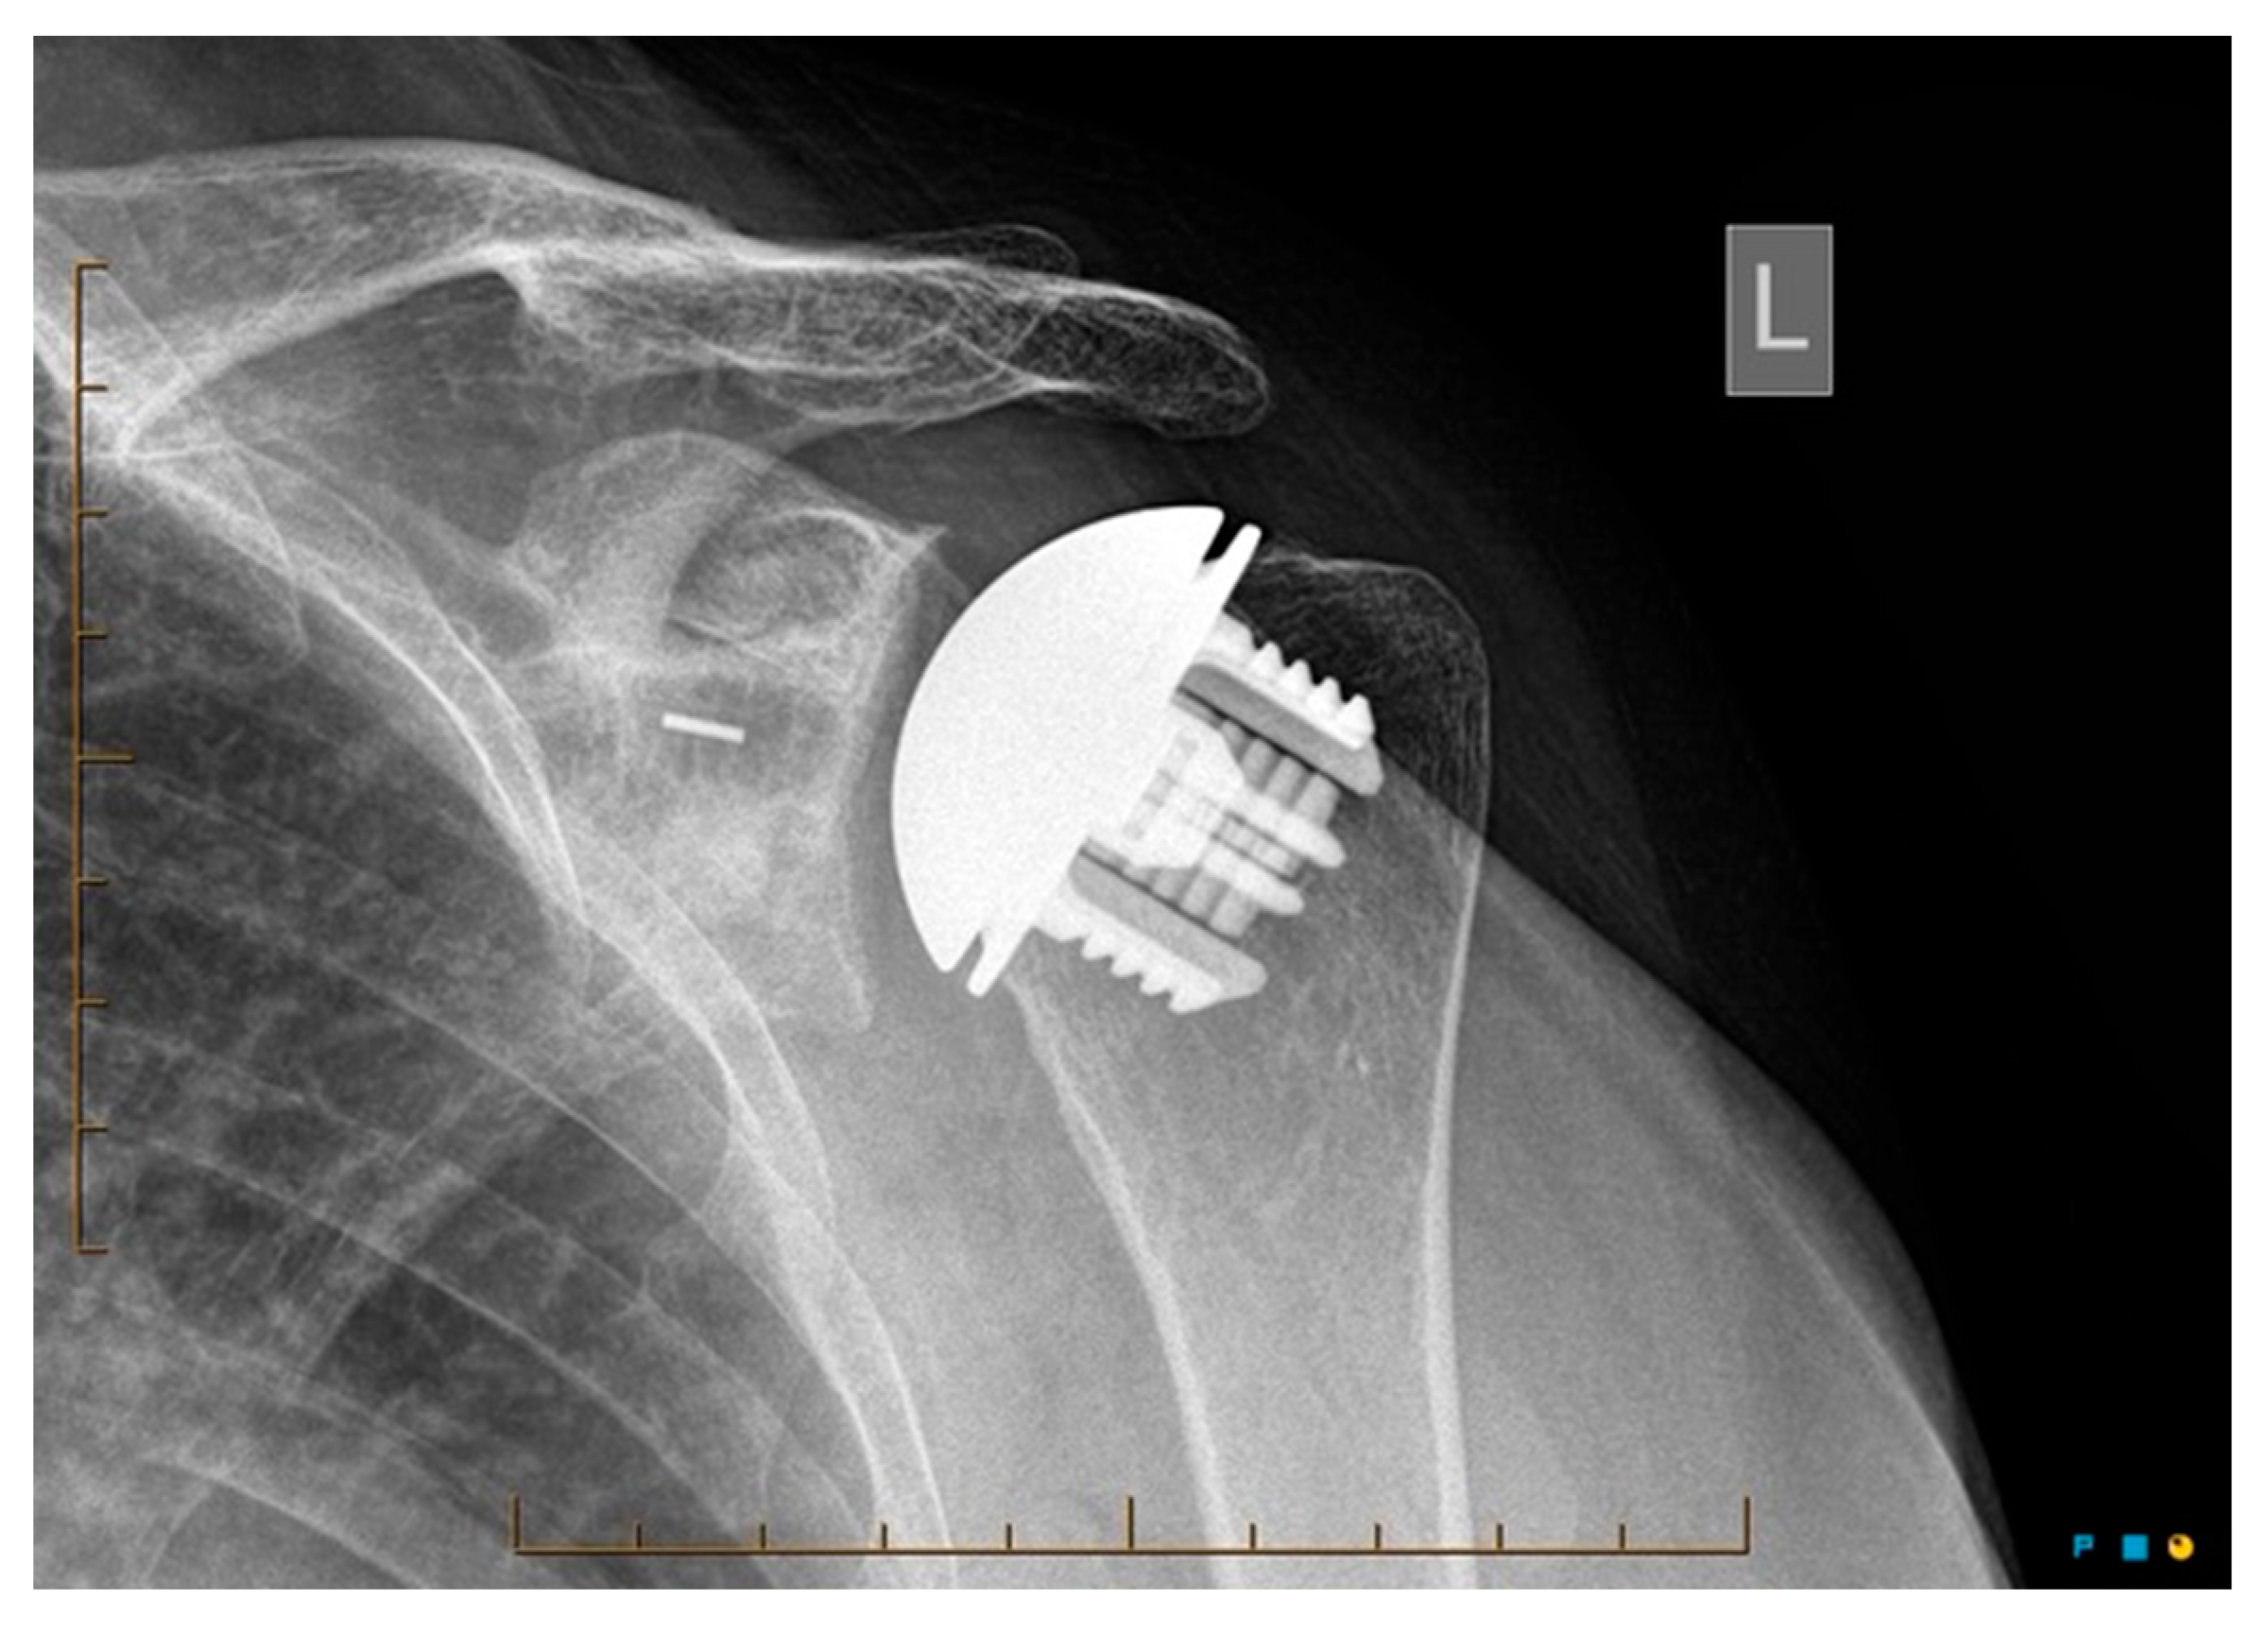

Medium-Term Clinical Outcomes of the Global Icon Stemless Shoulder System: Results of a 2-Year Follow-Up

2. Materials and Methods

3.2.2. Radiological Outcomes